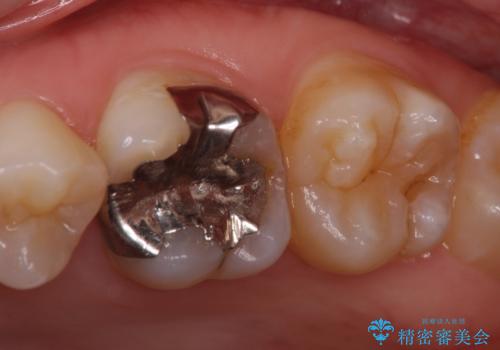

矯正治療後は、奥歯の虫歯や銀歯を補綴・修復治療することとしました。

PGA(ゴールド)クラウン、インレーの注意事項(リスク・副作用など)

- インレーおよびクラウンは脱離するリスクがあります

- 形成量はセラミックより少ないですが、歯の形成、修復後に歯に症状が出ることがあります

- 自費診療(保険適用外治療)となります